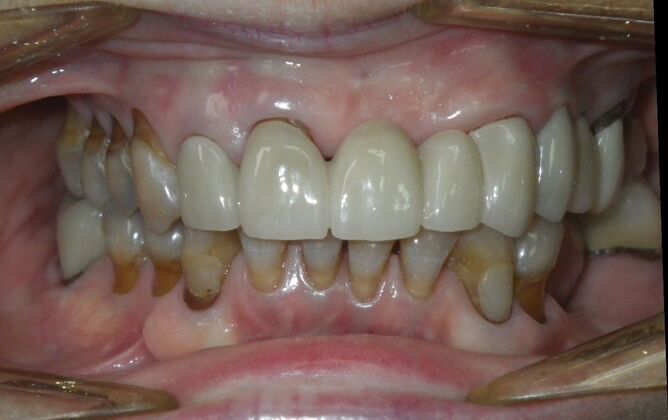

Cosmetic Changes with Veneers and Crown and Bridge: Case 6

Description

This patient had long term acidic erosion of upper and lower teeth eventually leading to loss of upper left central and lateral incisors. While she was somewhat happy with replacement of her front teeth with a removable appliance, she really desired to have something she didn't have to remove. So patient opted to be conservative with two single unit crowns as well as a four unit anterior bridge. These were fabricated using all ceramic without metal